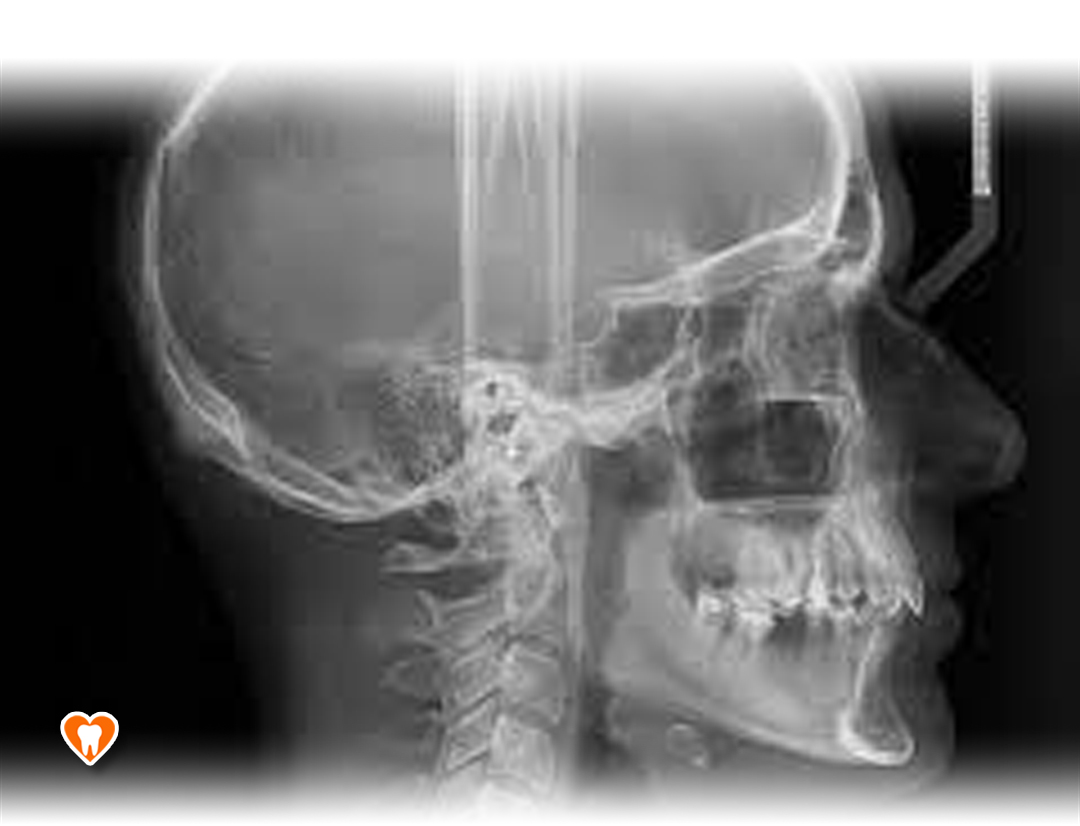

Zdjęcia radiologiczne:

• Cefalometryczne

Zdjęcie to umożliwia bardzo dokładną diagnostykę wad ortodontycznych oraz precyzyjne planowanie leczenia ortodontycznego. Jest metoda obrazowania części twarzowej czaszki, która uwidacznia zarówno struktury kostne, jak i skórę badanego.

W naszym gabinecie, dzięki zastosowaniu najnowszych urządzeń do radiowizjografii firmy Carestream, dostosowujemy indywidualnie do każdego pacjenta dawkę promieniowania, niezbędną do wykonania zdjęcia, jednocześnie minimalizując ją, aby każdy pacjent był bezpieczny.